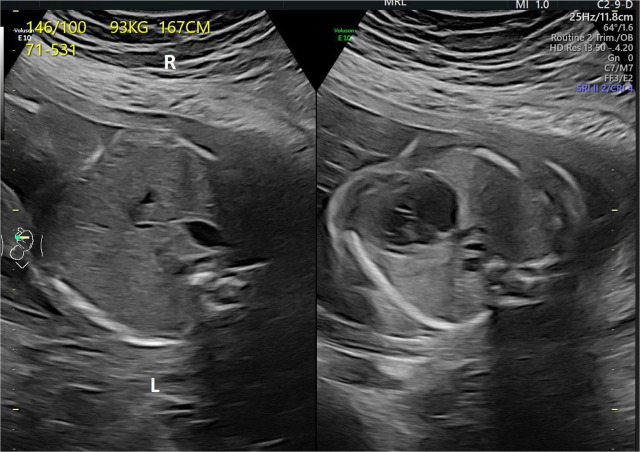

Total anomalous pulmonary venous connection is a rare congenital heart defect that can be diagnosed prenatally and might be very important for perinatal management. In addition to other cardiac abnormalities (levocardia, situs inversus, small left ventricle, double outlet right ventricle, parallel great vessels, and hypoplastic aortic arch), total anomalous pulmonary venous connection of a subdiaphragmatic type was diagnosed during a prenatal echocardiography examination in the second half of pregnancy. Fetal echocardiography monitoring showed no signs of congestive heart failure. The neonate was born at 38 weeks of gestation at our tertiary center. Postnatal echocardiography revealed significant progression in neonatal hemodynamics, and early cardiac surgery, involving repair of the pulmonary veins, pulmonary artery banding, and aortic arch reconstruction, was performed with a good outcome. This case is an excellent example of the value of prenatal echocardiography.

Abstract Image